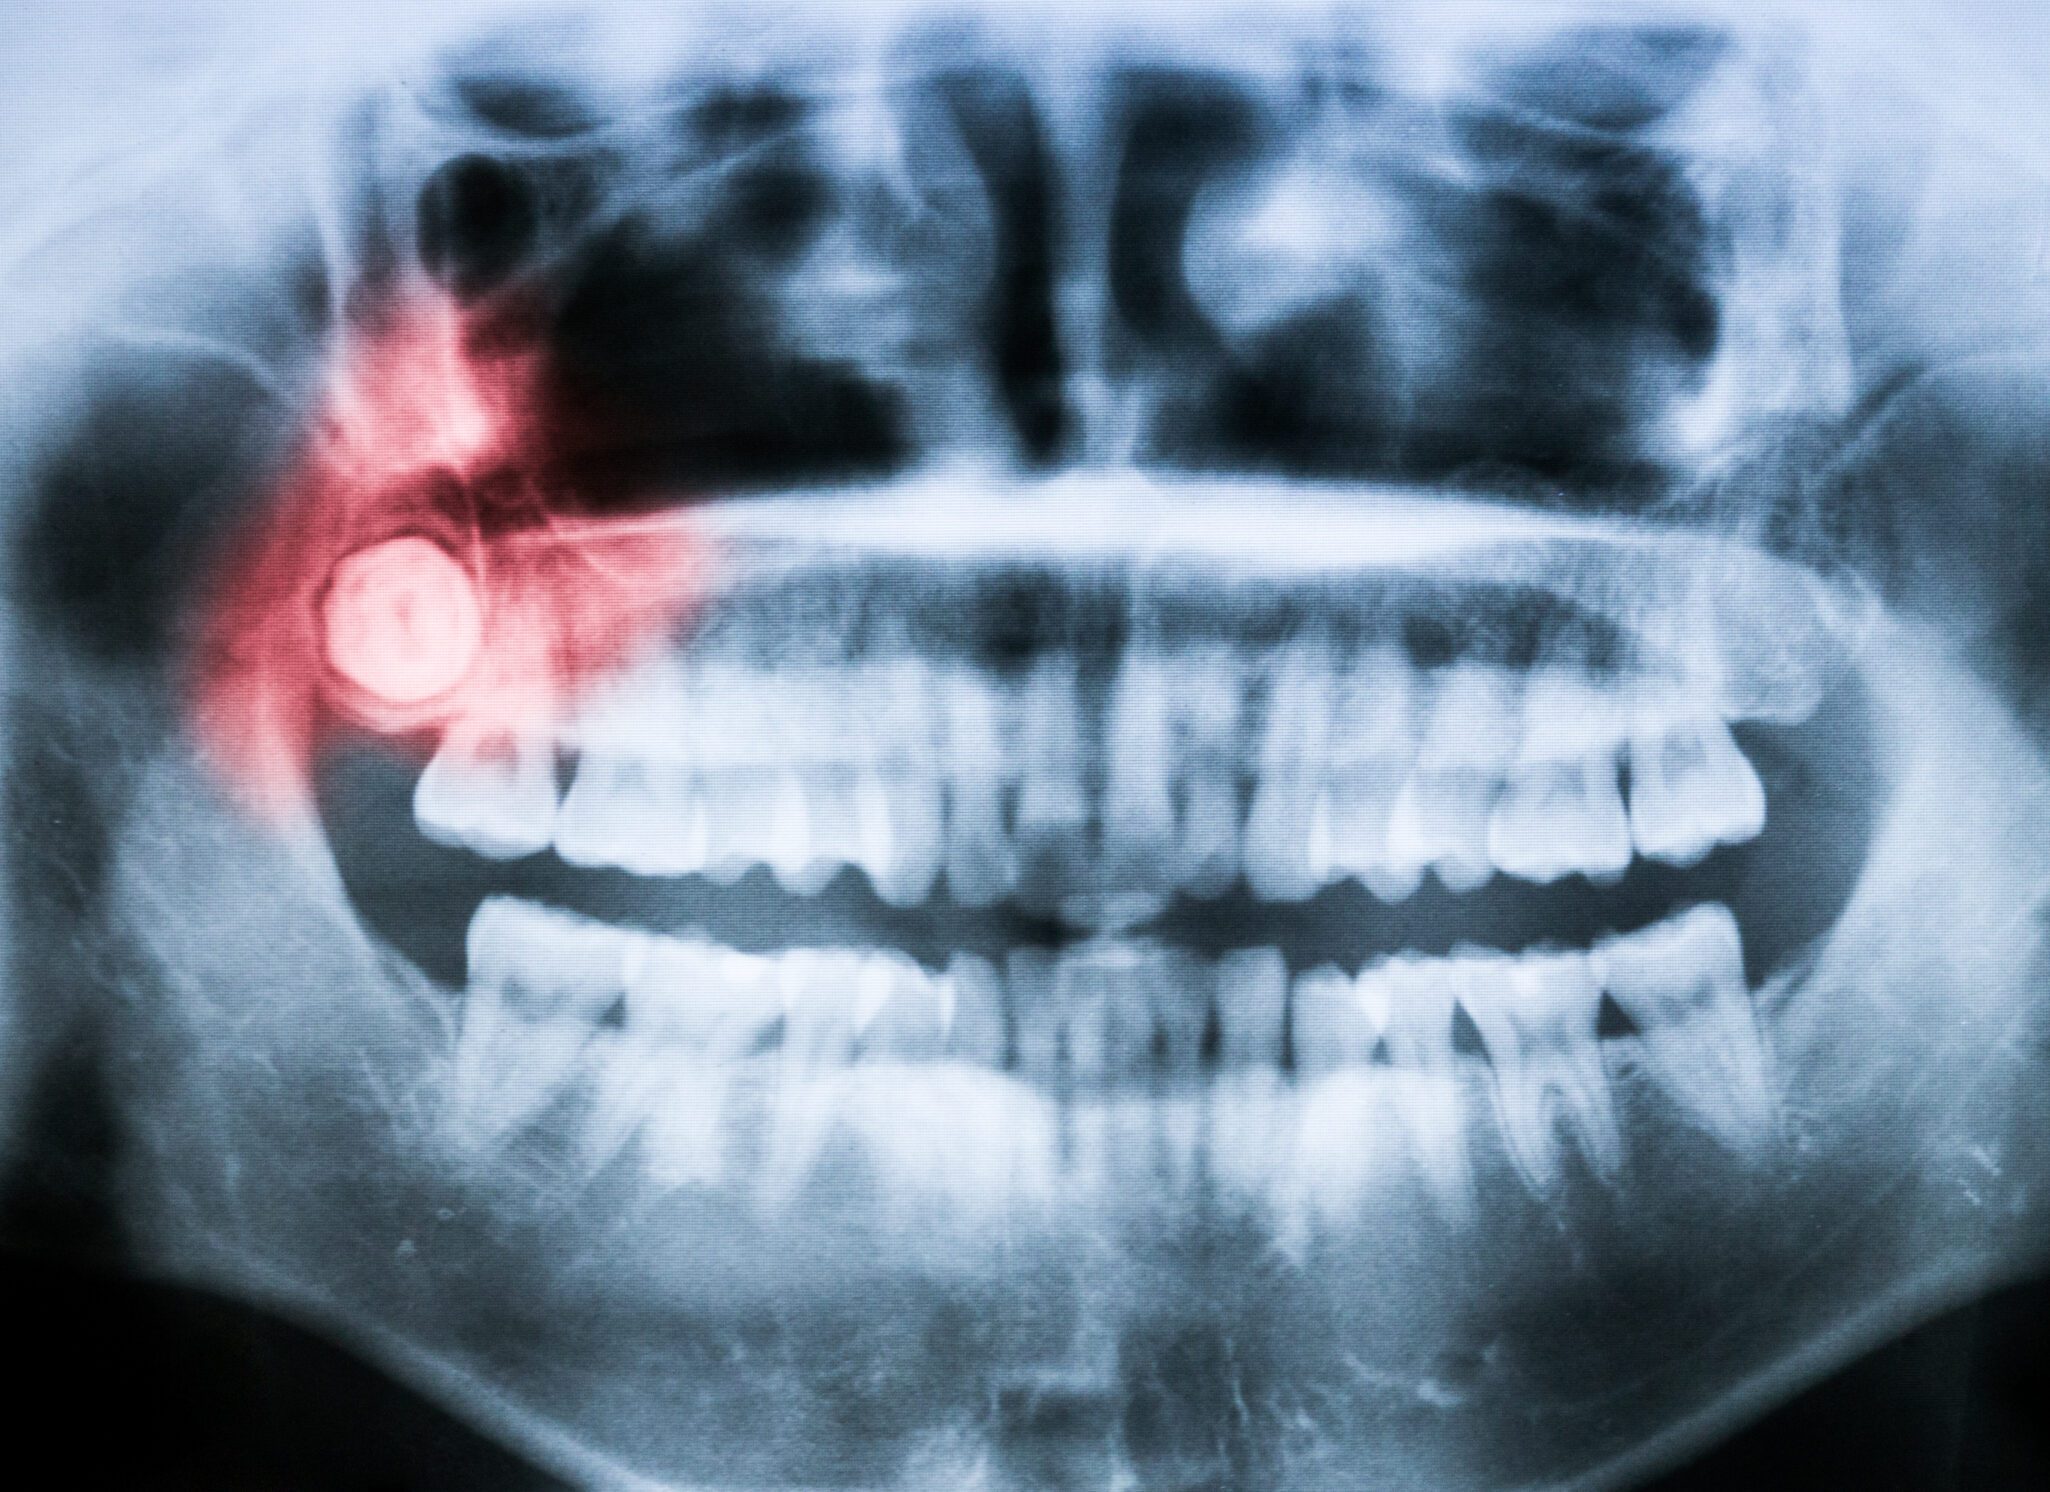

Sometimes a tooth causes more harm than good. When a tooth is severely decayed, infected, or damaged beyond repair, removing it is often the safest and kindest solution for your overall oral health.

You might need an extraction if you have severe tooth pain, an infection, a tooth that cannot be saved, or if teeth need to be removed to make space for orthodontic treatment.